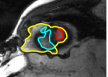

The problem above is a generalization of Horn & Schunck optical flow. Note that solving for the Horn & Schunck optical flow within each region separately does not lead to motions such that at the interface, they have equal normal components (see Figure 1), whereas the solution of (5) to be presented in subsequent sections does. Note that computing Horn & Schunck optical flow in each region requires boundary conditions (and typically they are chosen to be Neumann boundary conditions: and on ). Note that replacing these boundary conditions with the boundary constraint (6) does not specify a unique solution. Also, while Horn & Schunck optical flow computed on the whole domain naturally gives a globally smooth motion, which by default satisfies matching normals at the interface, this is not natural for the ventricles / myocardium, where different motions exist in the regions (see Figure 2), and the motions should not be smoothed across the regions.

![]() |

| image + boundary | global optical flow | our method | our method (motion decomp.) |